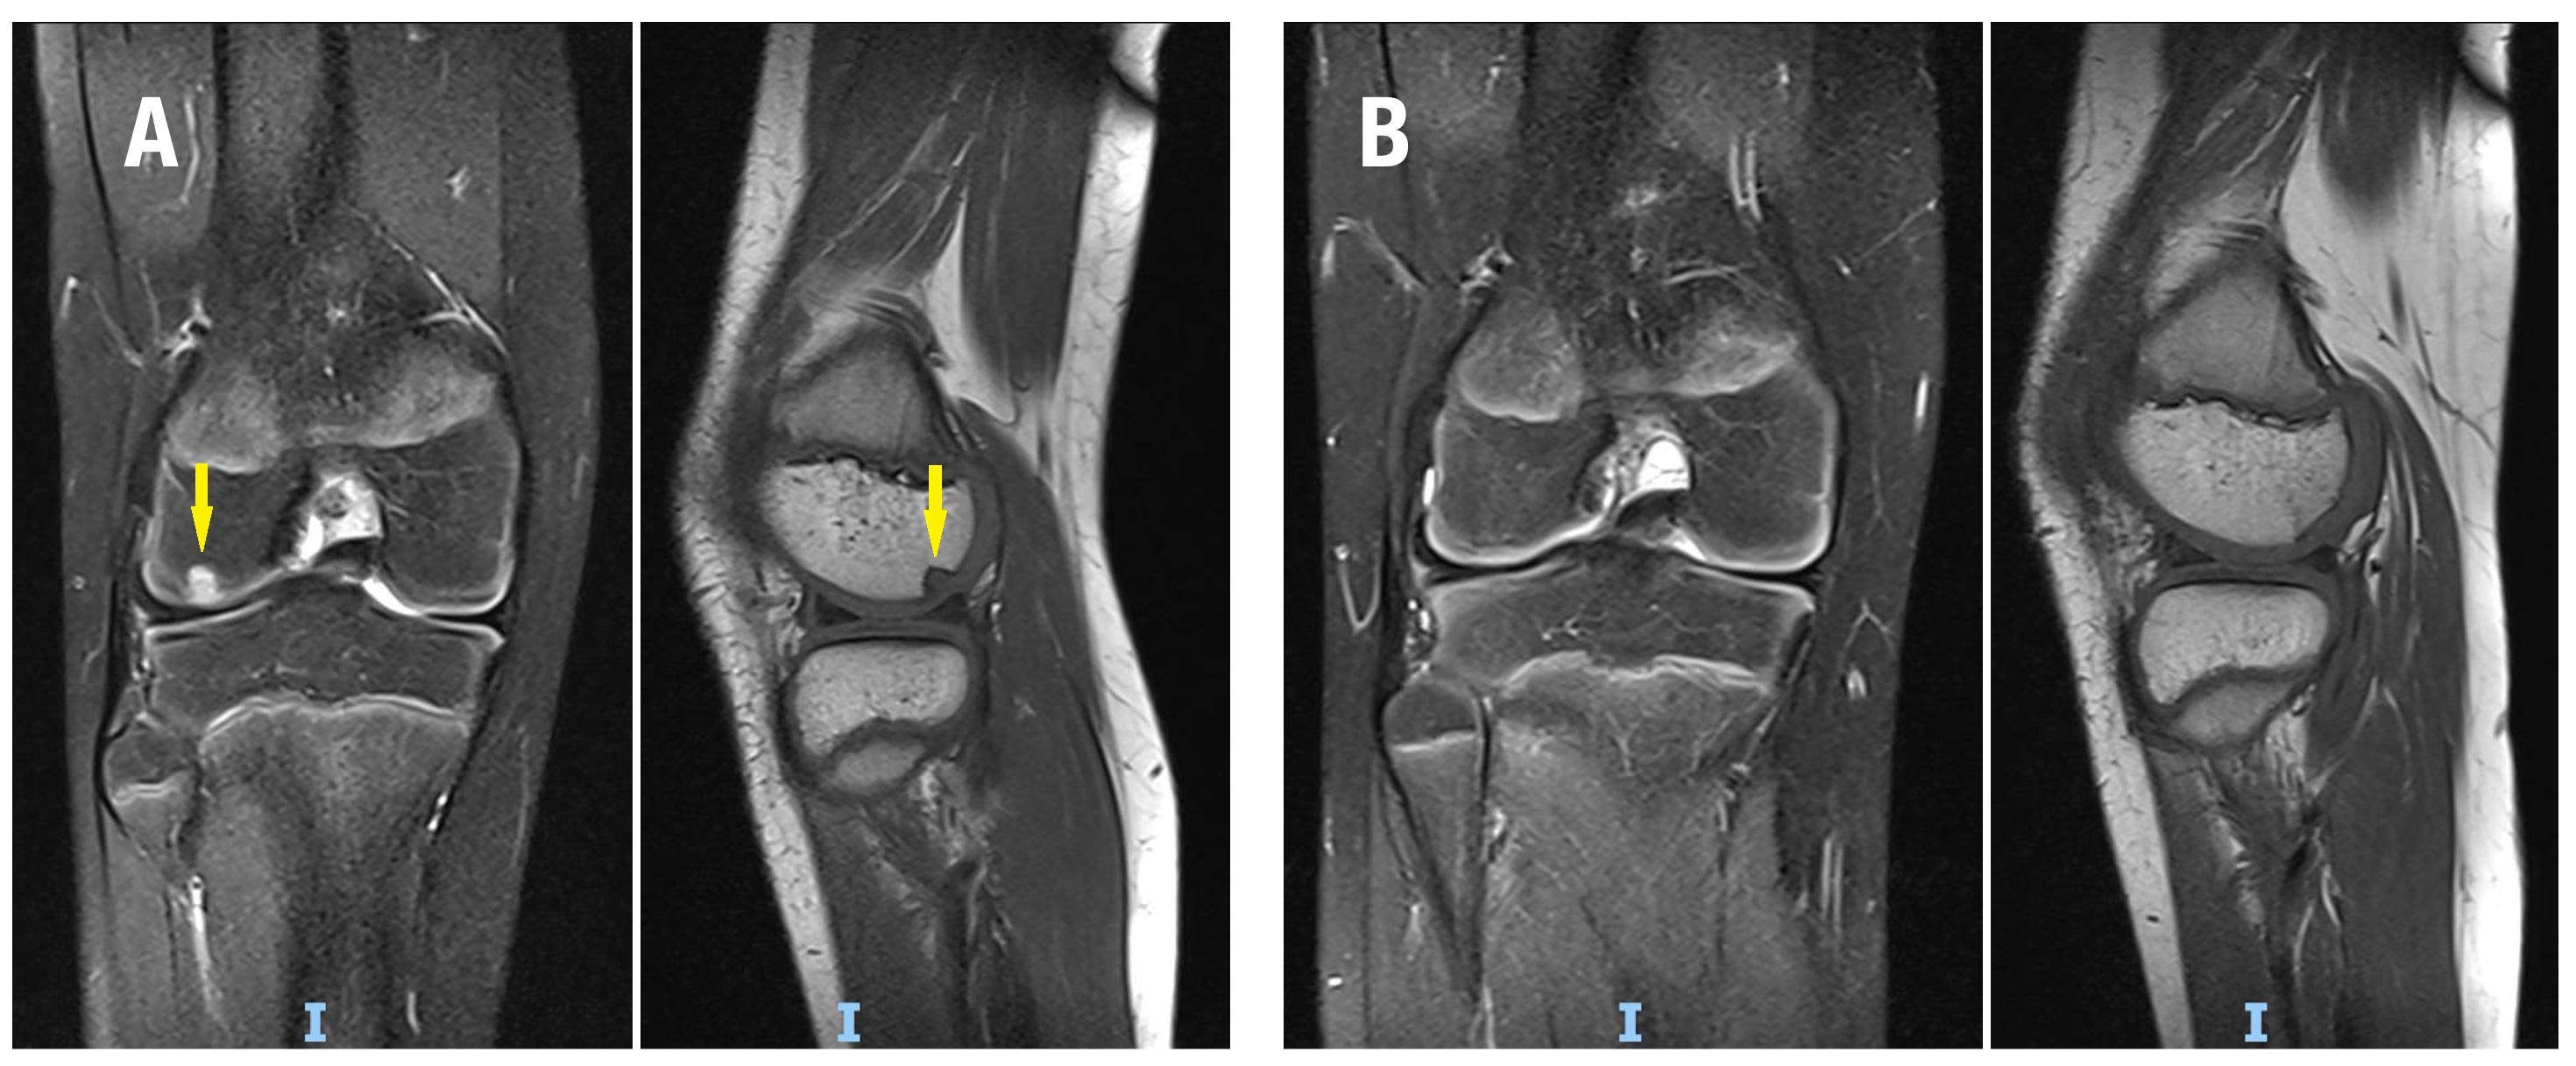

En promedio, se trasplantaron entre 1 y 3 injertos osteocondrales cilíndricos por rodilla, con un diámetro promedio de 8 mm (rango, 6-10 mm). Diecisiete rodillas se trataron para DC (Fig. 1) y 16 mediante FH (Fig. 2) de lesiones osteocondrales inestables. Las lesiones tratadas con la técnica DC tuvieron un tamaño promedio de 132 mm2, significativamente menor que las lesiones de FH, con un tamaño promedio de 404.1 mm2 (p <0.0001). El seguimiento promedio de la cohorte fue de 20.5 meses (rango, 6-80 meses). No se registraron complicaciones perioperatorias.

Figura 2. Fijación híbrida en una paciente de 14 años con osteocondritis disecante juvenil localizada en el cóndilo femoral medial. A) RNM DPFS sagital y coronal que demuestra lesión inestable de gran tamaño (flecha roja). B) Imagen intraoperatoria durante la colocación de un injerto osteocondral de 8 mm y 2 tornillos canulados. C) RNM a los 6 meses de evolución, luego del retiro del material de osteosíntesis, se evidencia la curación de la lesión y la incorporación del injerto. D) Radiografías de frente, túnel y perfil donde se observa la resolución completa de la lesión.